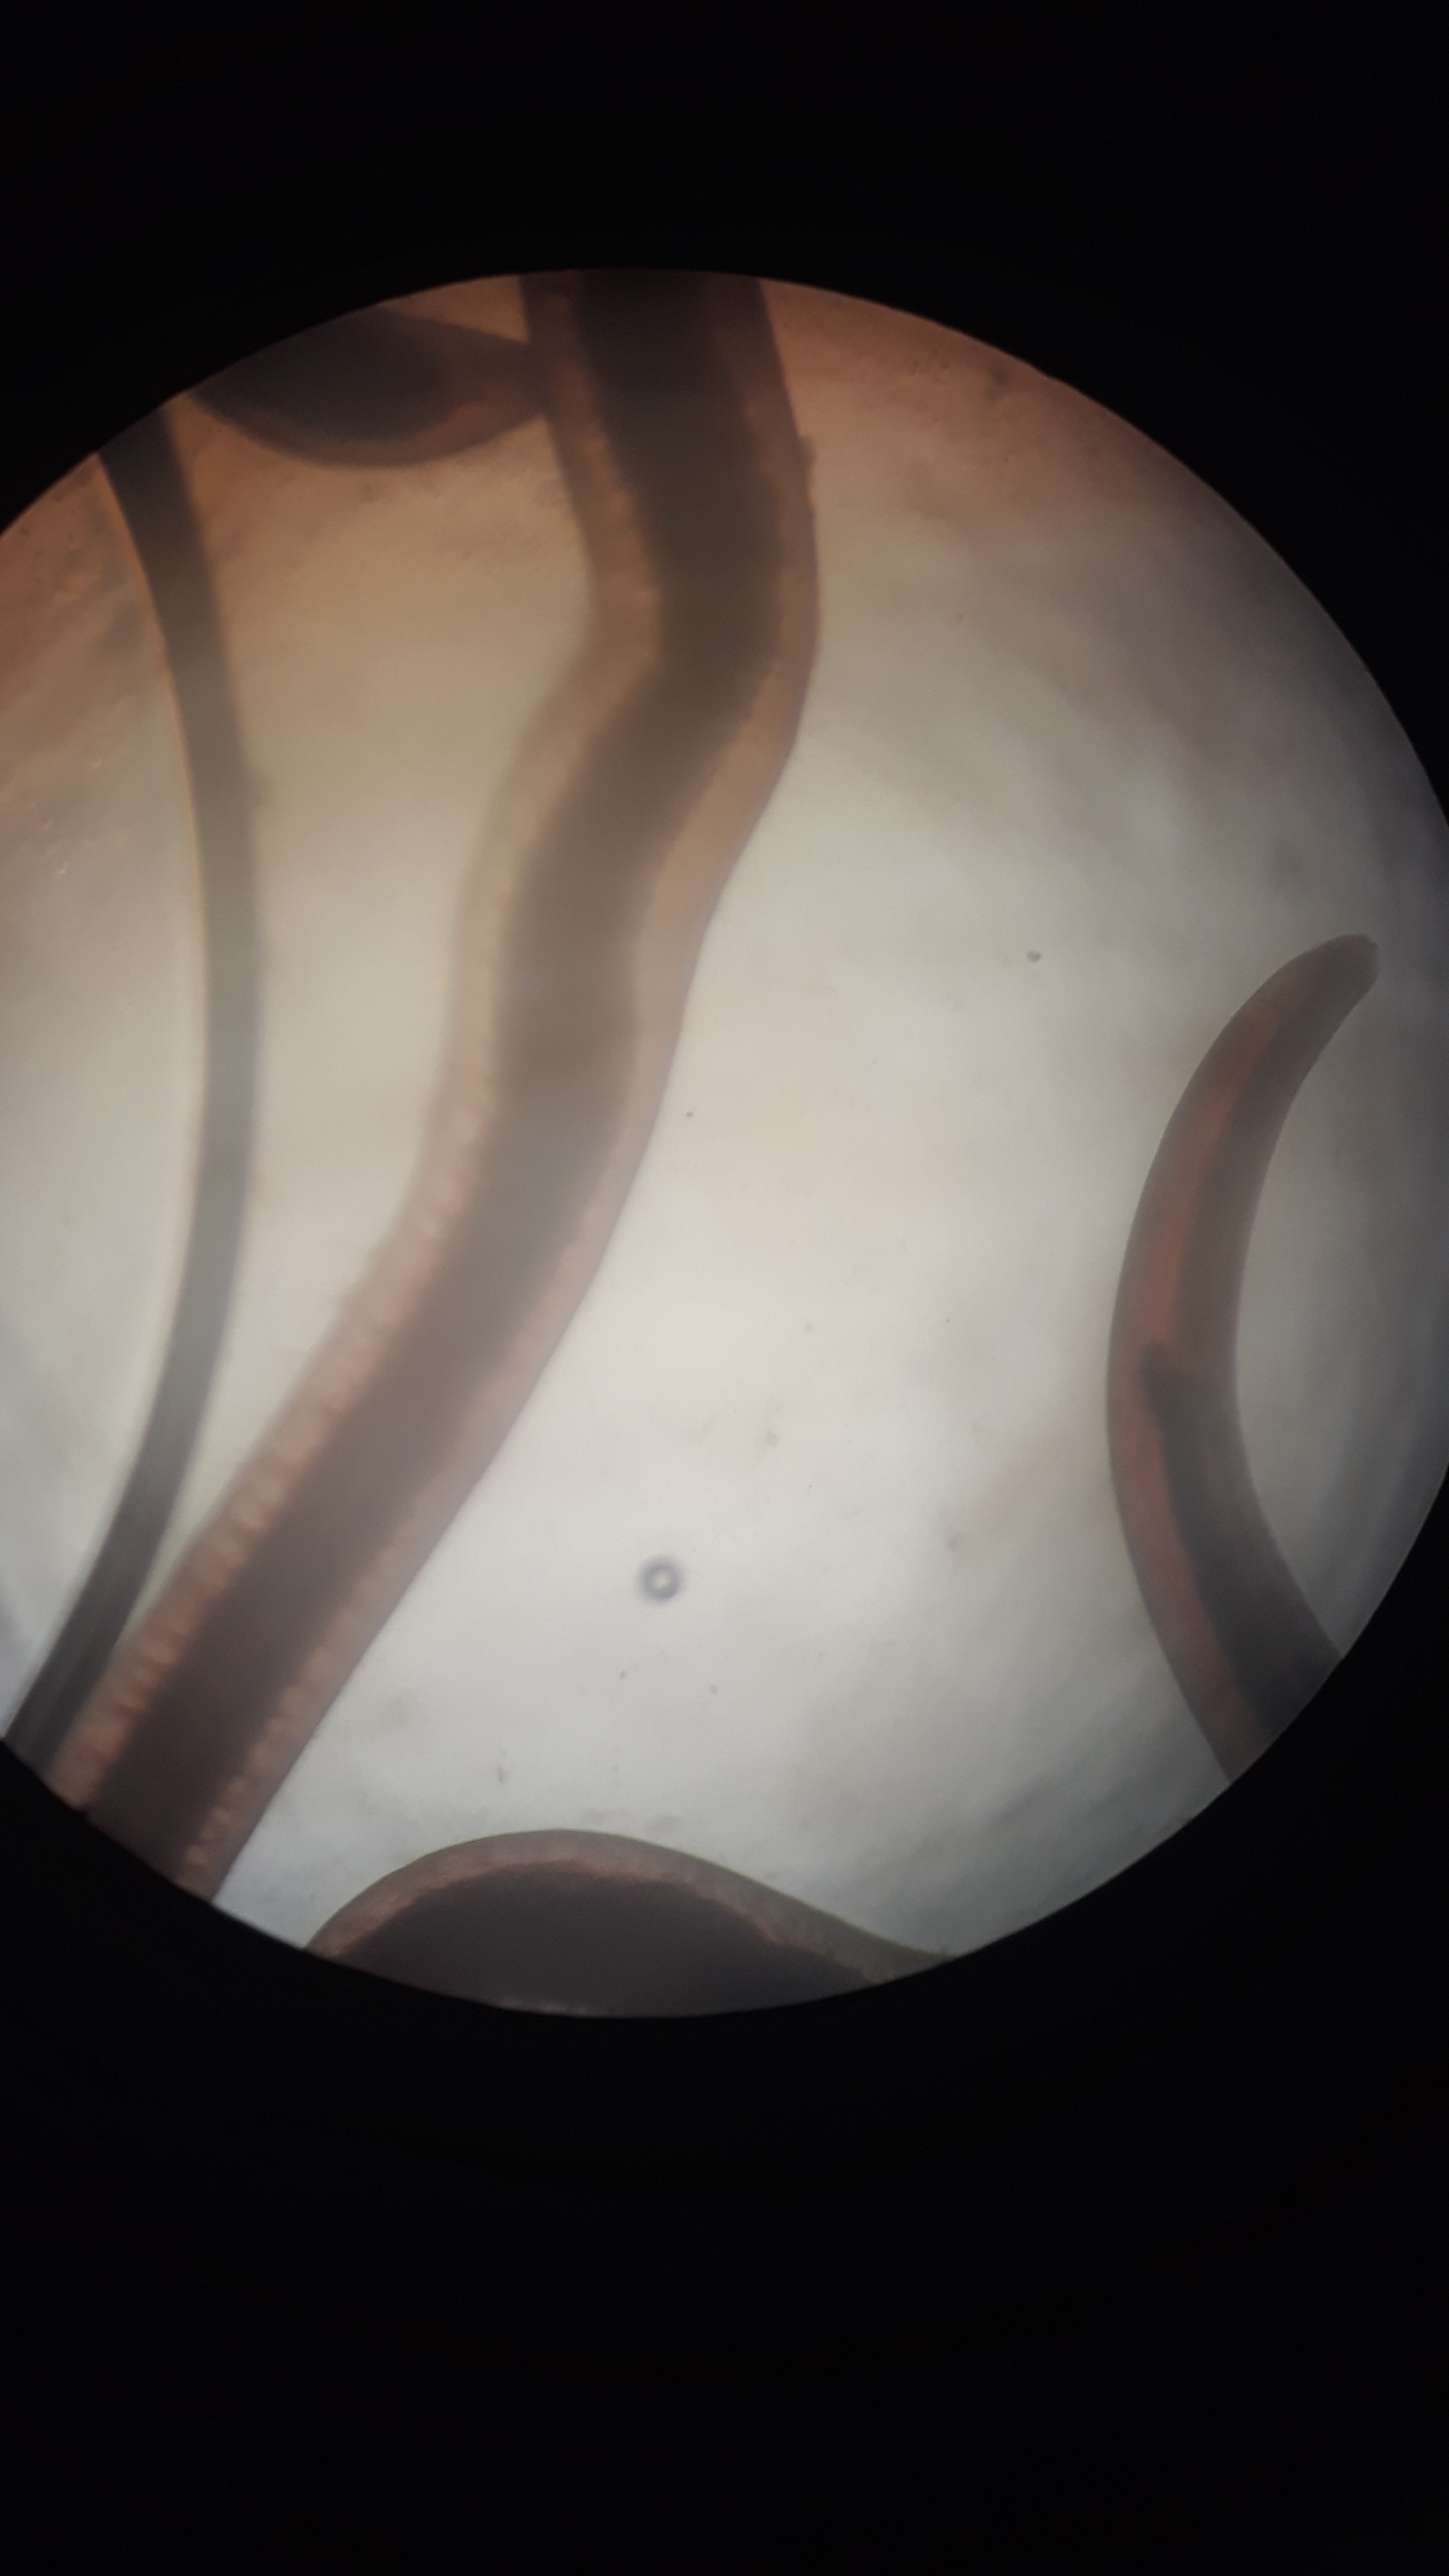

به گزارش روابط عمومی مرکز تحقیقات شیلاتی آبهای دور_ چابهار، کارگاه عملی روش های نمونه برداری و تشخیص بیماری های آبزیان در راستای آشنایی بهره برداران و دانشجویان با بیماری ها و نحوه تشخیص آنها و به مناسبت روز ترویج آموزش های فنی و حرفه ای و ارتقاء دانش بهره برداران با حضور خانم داوودی، رئیس بخش بهداشت و بیماری آبزیان استان، و امیر آرامون، مسئول آزمایشگاه بهداشت و بیماری آبزیان مرکز به عنوان مدرس دورهبرگزار گردید. ابتدا به اصول و روش های نمونه برداری جهت تشخیص آبزیان، معرفی انواع بیماری های ماهی و میگو و علائم و نشانه های بیماری در آنها و کنترل پاتوژن ها پرداخت. سپس ایشان در آزمایشگاه بهداشت و بیماری، روش های نمونه گیری از بافت میگو و ماهی و روش تشخیص سریع برخی پاتوژن ها و نحوه کشت باکتریایی و بررسی های انگلی و قارچی را به صورت عملی انجام داد.